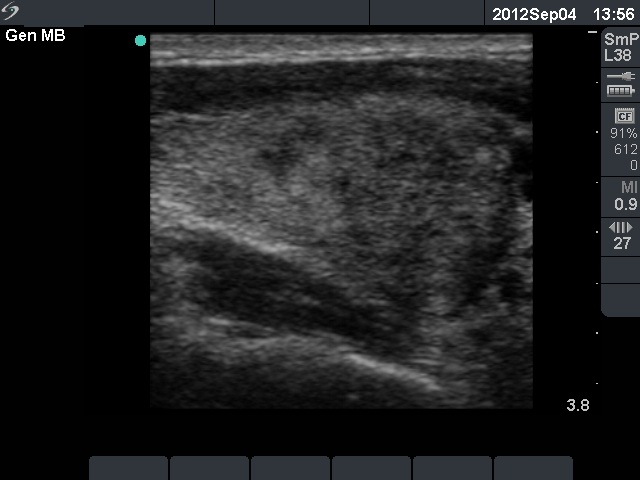

Follow-up examination 3 weeks later (3rd row of images):

Clinical presentation: the patient visited us again because of side effects of steroid - his blood pressure increased significantly. Otherwise she had no complaints.

Palpation: both thyroids were moderately firm but were not tender on palpation.

Functional state: subclinical hyperthyroidism with TSH-level 0.001 mIU/L, FT4 15.1 pM/L. ESR 28 mm/H, CRP 3.7 mg/L.

Ultrasonography: a relatively large hypoechogenic lesion with decreased vascularization has evolved in the previously intact right lobe. On the other hand, the hypoechogenic area in the left lobe significantly decreased in size and the vascularization normalized.